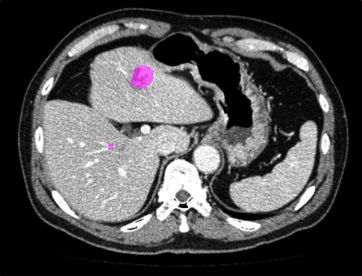

肝臓に発生した転移がんや嚢胞などの病変部位をCT画像解析により検出することを試みた.テクスチャ解析に基づいてEarth Movers DistanceによりCT値ヒストグラム間距離を算出する.病変組織と健常組織の特徴を機械学習によって識別するアルゴリズムを提案した.